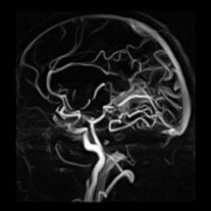

Beyin anjiyosunda MR anjiografi vücuttaki damarların görüntülendiği bir MR çalışmasıdır. Manyetik rezonans anjiografi klasik manyetik rezonans (MR) görüntüleme ile anjiografiyi birleştirerek vücudumuzdaki damarlar hakkında deyatlı bilgi veren bu yöntem birçok hastalığın tanısında yardımcı oluyor.

MR teknolojisi kullanarak damar hastalıklarının tanısında son yıllarda oldukça sık kullanılmaktadır. İlaç verilmeden büyük ana damarlar rahatça görüntülenebilmektedir.

Anjiyografi beyin damarlarının görüntülenmesinde de kullanılan bir yöntemdir. Boyunda ve beyin damarlarında tıkanıklık olup olmadığını tespit etmek için beyin anjiyosu yapılmaktadır. Özel ilaçlar kullanılarak görüntü kalitesini arttırarak, damar yapılara ait ince ayrıntıların görüntülendiği beyin anjiyosunun en önemli avantajı kateter ve BT anjiografide kullanılan kontrast maddelere bağlı alerjik reaksiyon riskinin oldukça düşük olmasıdır. Üstelik diğer anjiografi yöntemlerine göre inceleme süresi ve maliyeti daha düşüktür. Beyin damar tıkanıklığı, beyin ve beyinciği besleyen, boyunda ve kafa içindeki damarlarda oluşan tıkanıklıkları anlatır. Çeşitli nedenlerden dolayı beyin damarlarında tıkanma olabilir. Boyunda şah damarı ya da küçük damarların tıkanması, çeşitli beyin hastalıklarına ve felce neden olabiliyor. Damar hastalıklarına, daha çok ileri yaştaki kişilerde rastlanıyor.